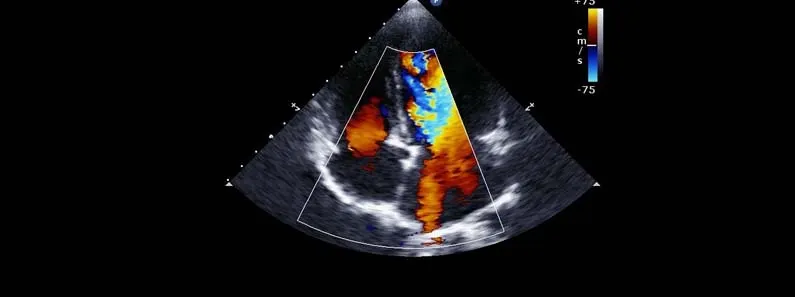

The Colour Doppler sonography is a kind of ultrasound technique. It helps to see how blood is moving in the Colour Doppler sonography. This technique looks at the blood flow in the veins and arteries.

The Colour Doppler sonography is different from an ultrasound. The Colour Doppler sonography shows which way the blood is going how fast it is moving and what the pattern of the blood movement is. This information from the Colour Doppler sonography helps the doctors find any blockages in the blood vessels or if the blood vessels are too narrow or if there are problems, with the valves or if the blood is not circulating properly with the help of Colour Doppler sonography.

Colour Doppler sonography is used for things. It is a type of ultrasound test. Colour Doppler sonography helps doctors see blood flowing through the blood vessels. Doctors use Colour Doppler sonography to check the blood vessels. They use Colour Doppler sonography to see if the blood vessels are working properly. Colour Doppler sonography is very helpful. Doctors like to use Colour Doppler sonography because it helps them find problems, with the blood vessels. Doctors use Colour Doppler sonography to look at the blood flow in the arteries and the veins. This helps them find out if there are any problems with the blood circulation.

Colour Doppler sonography can detect things like blocked vessels or varicose veins. It can also find blood clots. See if the organs and the limbs are getting enough blood supply from the Colour Doppler sonography. The Colour Doppler sonography is very useful for the doctors to figure out what is going on with the blood flow, in the arteries and the veins.

Yes. A normal ultrasound is really good at showing what the organs and tissues look like.. Colour Doppler does that and also shows where the blood is going and how fast it is moving. This makes Colour Doppler really useful for problems with the blood vessels and the way the blood circulates in the body. Colour Doppler is especially helpful, for people who have problems or issues with their circulation.